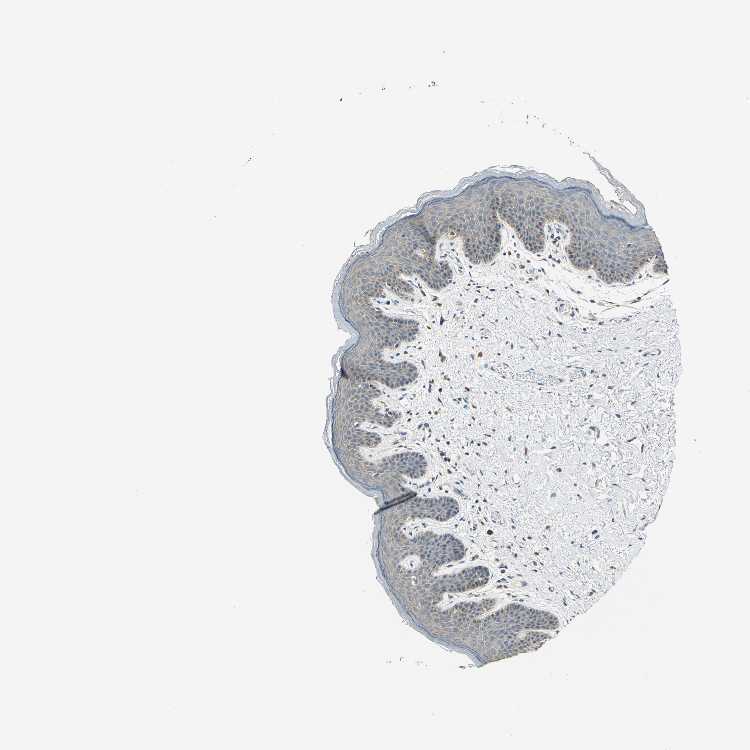

SKIN 1 - Antibody stainingi

Antibody staining in the annotated cell types in the current human tissue is reported as not detected, low, medium, or high, based on conventional immunohistochemistry profiling in selected tissues. This score is based on the combination of the staining intensity and fraction of stained cells.

Each image is clickable and will lead to virtual microscopy that enables deeper exploration of all samples and also displays staining intensity scores, fraction scores and subcellular localization as well as patient and tissue information for each sample.

Antibody HPA001648Antibody HPA005631Antibody HPA059583

Langerhans LowLowNot detected

Fibroblasts Not detectedLowNot detected

Keratinocytes LowLowMedium

Melanocytes LowLowNot detected

SKIN 2 - Antibody stainingi

Epidermal cells LowLowHigh